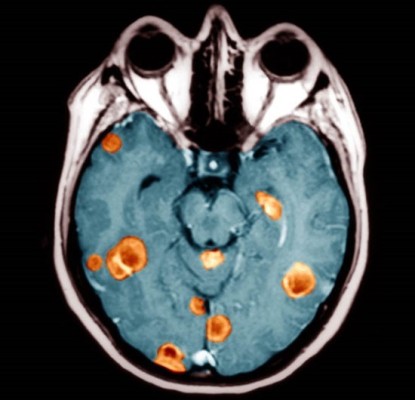

뇌종양은 뇌조직이나 뇌를 싸고 있는 막에서 발생된 종양과 머리뼈나 주변 구조물에서 멀리 떨어진 부위에서 뇌조직이나 뇌막으로 전이된 종양을 말합니다. 또, 뇌종양은 양성과 악성으로 나눌 수 있는데요. 양성 뇌종양은 성장속도가 느리고 주위 조직과의 경계가 뚜렷한 특성을 지니고 있습니다. 악성 뇌종양은 뇌암이라고도 말하며, 성장속도가 빠르고 주위 조직으로의 침투 능력이 강하여 주변의 정상 뇌조직을 빠른 속도로 파괴합니다.

뇌종양의 가장 흔한 증상은 두통입니다. 간질 발작이 나타나거나 점진적인 운동 및 감각 능력이 소실됩니다. 오심, 구토가 나타날 수 있으며 시력이 손실되거나 복시가 나타날 수 있습니다. 또한, 뇌종양의 크기와 위치에 따라 다양한 증상이 나타날 수 있습니다. 뇌종양을 의심하게 하는 증상들은 다음과 같습니다.